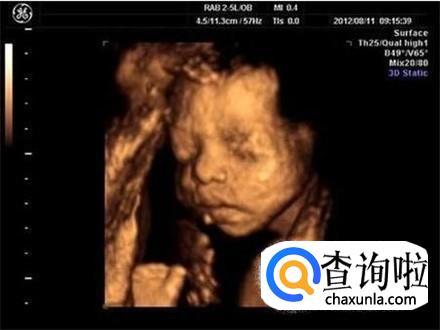

从专业技术的角度上来说,四维彩超是确实能够看到胎儿的性别的,因为和其他的超声波检查项目相比较的话,四维彩超能够实时显示宝宝的动态,从而能够看出性别。